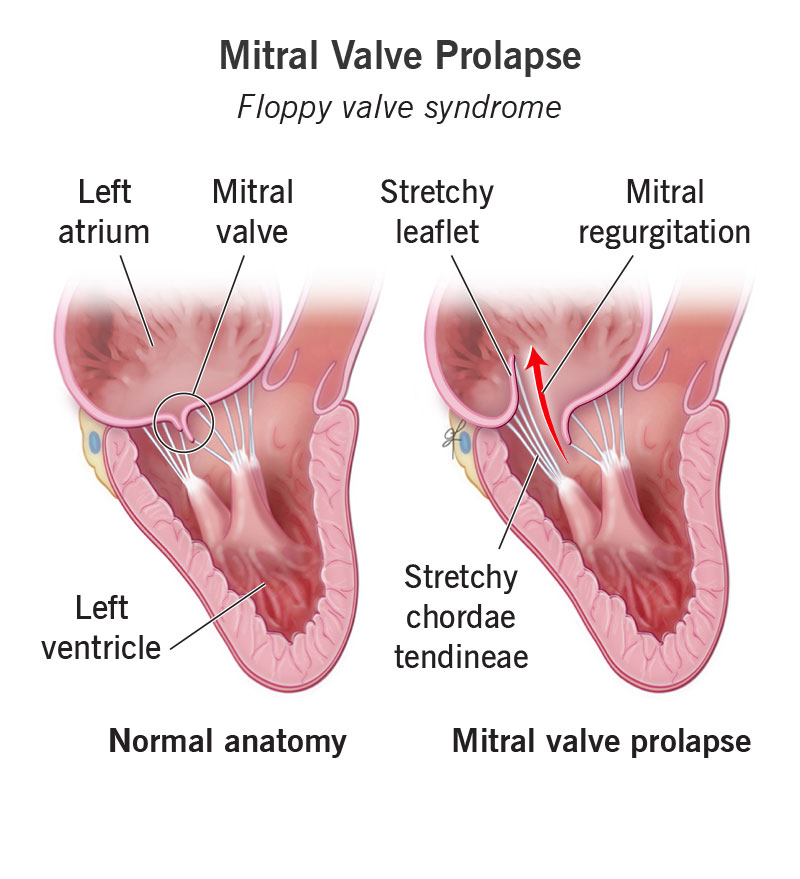

Mitral Valve Prolapse: Causes And Symptoms - Ask The Nurse Expert

askthenurseexpert.com

askthenurseexpert.com